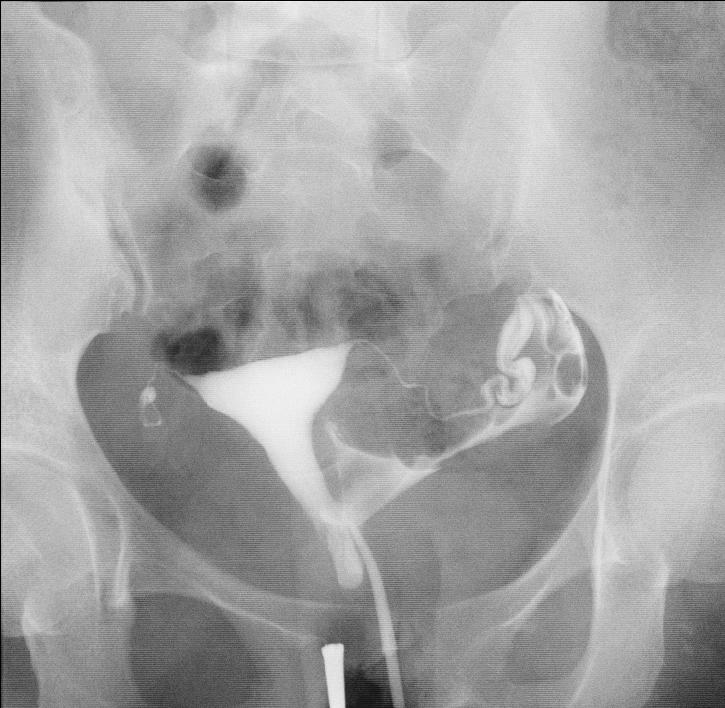

2019年2月27日,由于基层大夫跟我关系很好,把她介绍到我这里看看,来时就说“能看就看,如果花费太大,就不看了”,我就先让她做了一个无痛不插管子宫输卵管造影检查,结果显示:左侧输卵管通而不畅,右侧输卵管不通,通过片子,我觉得她的右侧输卵管已经没有希望,来的太晚了,剩下的左侧输卵管还不是完全通畅的,目前的情况是想花钱少又想怀孕,就好好听话,好好治疗,不然宫外孕就更惨了。

当日她经过激烈的家庭讨论,听说硬是咬牙跺脚从牙缝中挤出来的一万块钱,同意做输卵管介入疏通治疗,我也很感动,决定为他们亲自上手术,最后的治疗的结果是这样的:我觉得她如果能真正遵从医嘱,三个月到半年内应该能够顺利怀孕。